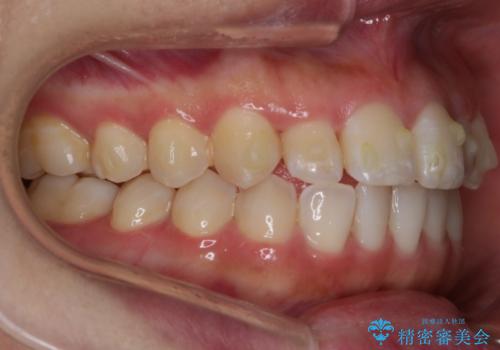

【非抜歯】部分矯正でも治る 前歯の反対咬合

- 前歯にガタつきを主訴にご来院されました。

奥歯の嚙み合わせに問題がほとんどみられなかったため、インビザライン ライトパッケージでの部分矯正を行うこととなりました。

今回のケースでは奥歯の噛み合わせに問題がほぼみられなかったため、前歯の位置のみに焦点を当て部分矯正を行いました。